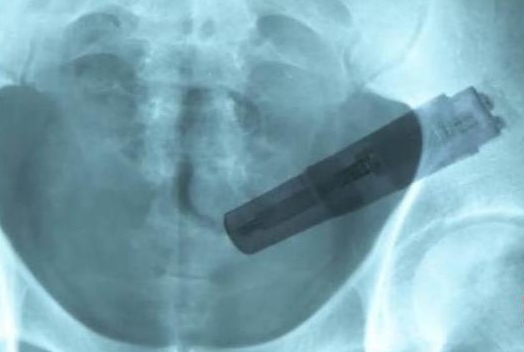

"Se poate vedea perfect un obiect mare, care i-a rămas blocat în intestinul gros", a spus, conform celor de la jurnalul.ro, asistenta care l-a tratat pe pacient! Făcea referire la un vibrator, care, culmea, a şi pornit în timpul manevrelor de "deblocare".

"Constipaţia" de care se plângea bărbatul putea să-i aducă probleme serioase dacă nu se prezenta mai repede la spital!